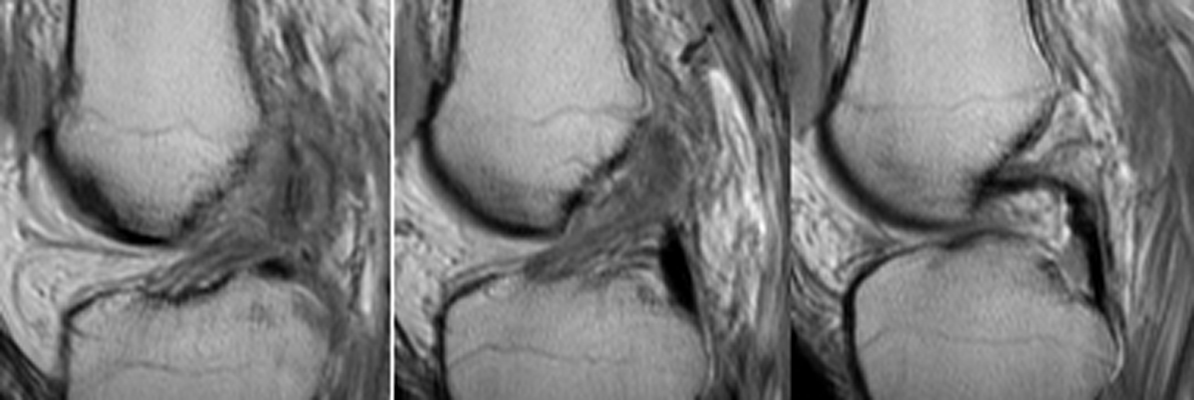

Frontal radiographs of the knee which reveal a small fleck of bone adjacent to the lateral aspect of the lateral tibial plateau. This "lateral capsular sign" is a simple radiographic finding visible on the routine AP knee x-ray, which indicates severe lateral capsular injury and should alert the examiner to the possibility of ACL tear. The fleck of bone represents an avulsion of the meniscotibial portion of the middle one-third of the lateral capsular ligament. It most commonly implies a disruption of the capsular ligament and the ACL. A-B Radiographs. C. MRI confirms the diagnosis of ACL tear.

AP knee - Click on the image for a larger versionAAP knee - Click on the image for a larger versionB - Click on the image for a larger versionC